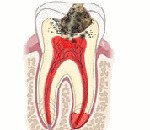

Серозный периодонтит. Острое воспаление околокорневой соединительнотканной оболочки зуба, характеризующееся заполнением экссудатом белковой природы щели между корнем зуба и стенкой альвеолы. Пациенты жалуются на появление резкой болезненности при накусывании на причинный зуб. Слизистая оболочка в проекции верхушек корней гиперемирована, отечна, болезненна. Диагностика серозного периодонтита включает клинический осмотр, рентгенологическое исследование, ЭОД. При выявлении патологии показано эндодонтическое лечение, включающее удаление путридных масс из корневых каналов, инструментальную и медикаментозную обработку, стерилизацию и обтурацию каналов эндогерметиком.

При серозном периодонтите микроскопически выявляют повышение проницаемости сосудов гаверсовых каналов, стаз, тромбоз, отек основного вещества соединительной ткани, дистрофические изменения нервных волокон, признаки начальной стадии дезорганизации коллагена. Наблюдается активизация остеокластов. В патологический очаг устремляются защитные клетки крови - нейтрофилы, лимфоциты. Экссудат при серозном периодонтите состоит преимущественно из ферментов, альбуминов, иммуноглобулинов. Структура периодонтальной щели в большинстве случаев не нарушена.